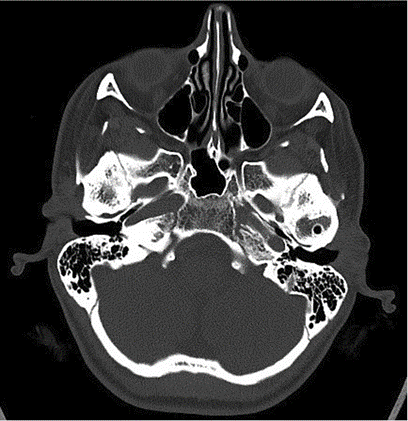

We asked him to get a preliminary CT scan to confirm our suspicion that showed a classical picture of fusion of the joint to the skull base.

In the CT scan image shown here, you can see a large boulder-like enlargement of the joint. This is the ankylotic mass.